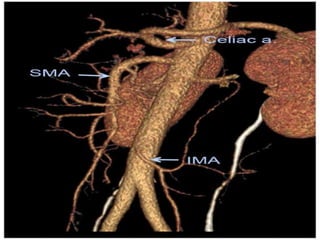

Anatomy Of Splanchnic Circulation

The splanchnic or mesenteric arteries

comprise

 Celiac artery

 Superior mesenteric artery

 Inferior mesenteric artery

Major collateral circuits



Pancreaticoduodenal

arcade

Celiac

artery

SMA

Arc Of Riolan

Marginal Artery Of

Drummond

IMA